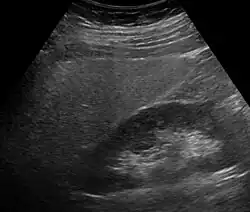

Eine Leberverfettung fällt meistens in einer Sonographie durch Vergrößerung und erhöhte Echogenität im Vergleich mit der Niere[12] sowie durch eine plumpe Form oder in einer Computertomographie oder Magnetresonanztomographie auf. Wenn aus anderen Gründen eine Biopsie der Leber durchgeführt wird, lässt sich die Fettleber auch histologisch sichern. Laborchemisch lässt sich kein sicherer Nachweis führen, allerdings fallen oft leicht erhöhte Transaminasen und eine erhöhte γ-GT auf.[13] Es gibt auch die Möglichkeit, mit Hilfe von Körpergröße, Körpergewicht, γ-GT, Triglyceriden und Bauchumfang den Fettleber-Index zu berechnen, der die Wahrscheinlichkeit für das Vorliegen einer Fettleber vorhersagen kann.[14] Der Schweregrad kann mittels spezieller Kernspintomographie- oder Elastographie-Methoden bestimmt werden.[15]